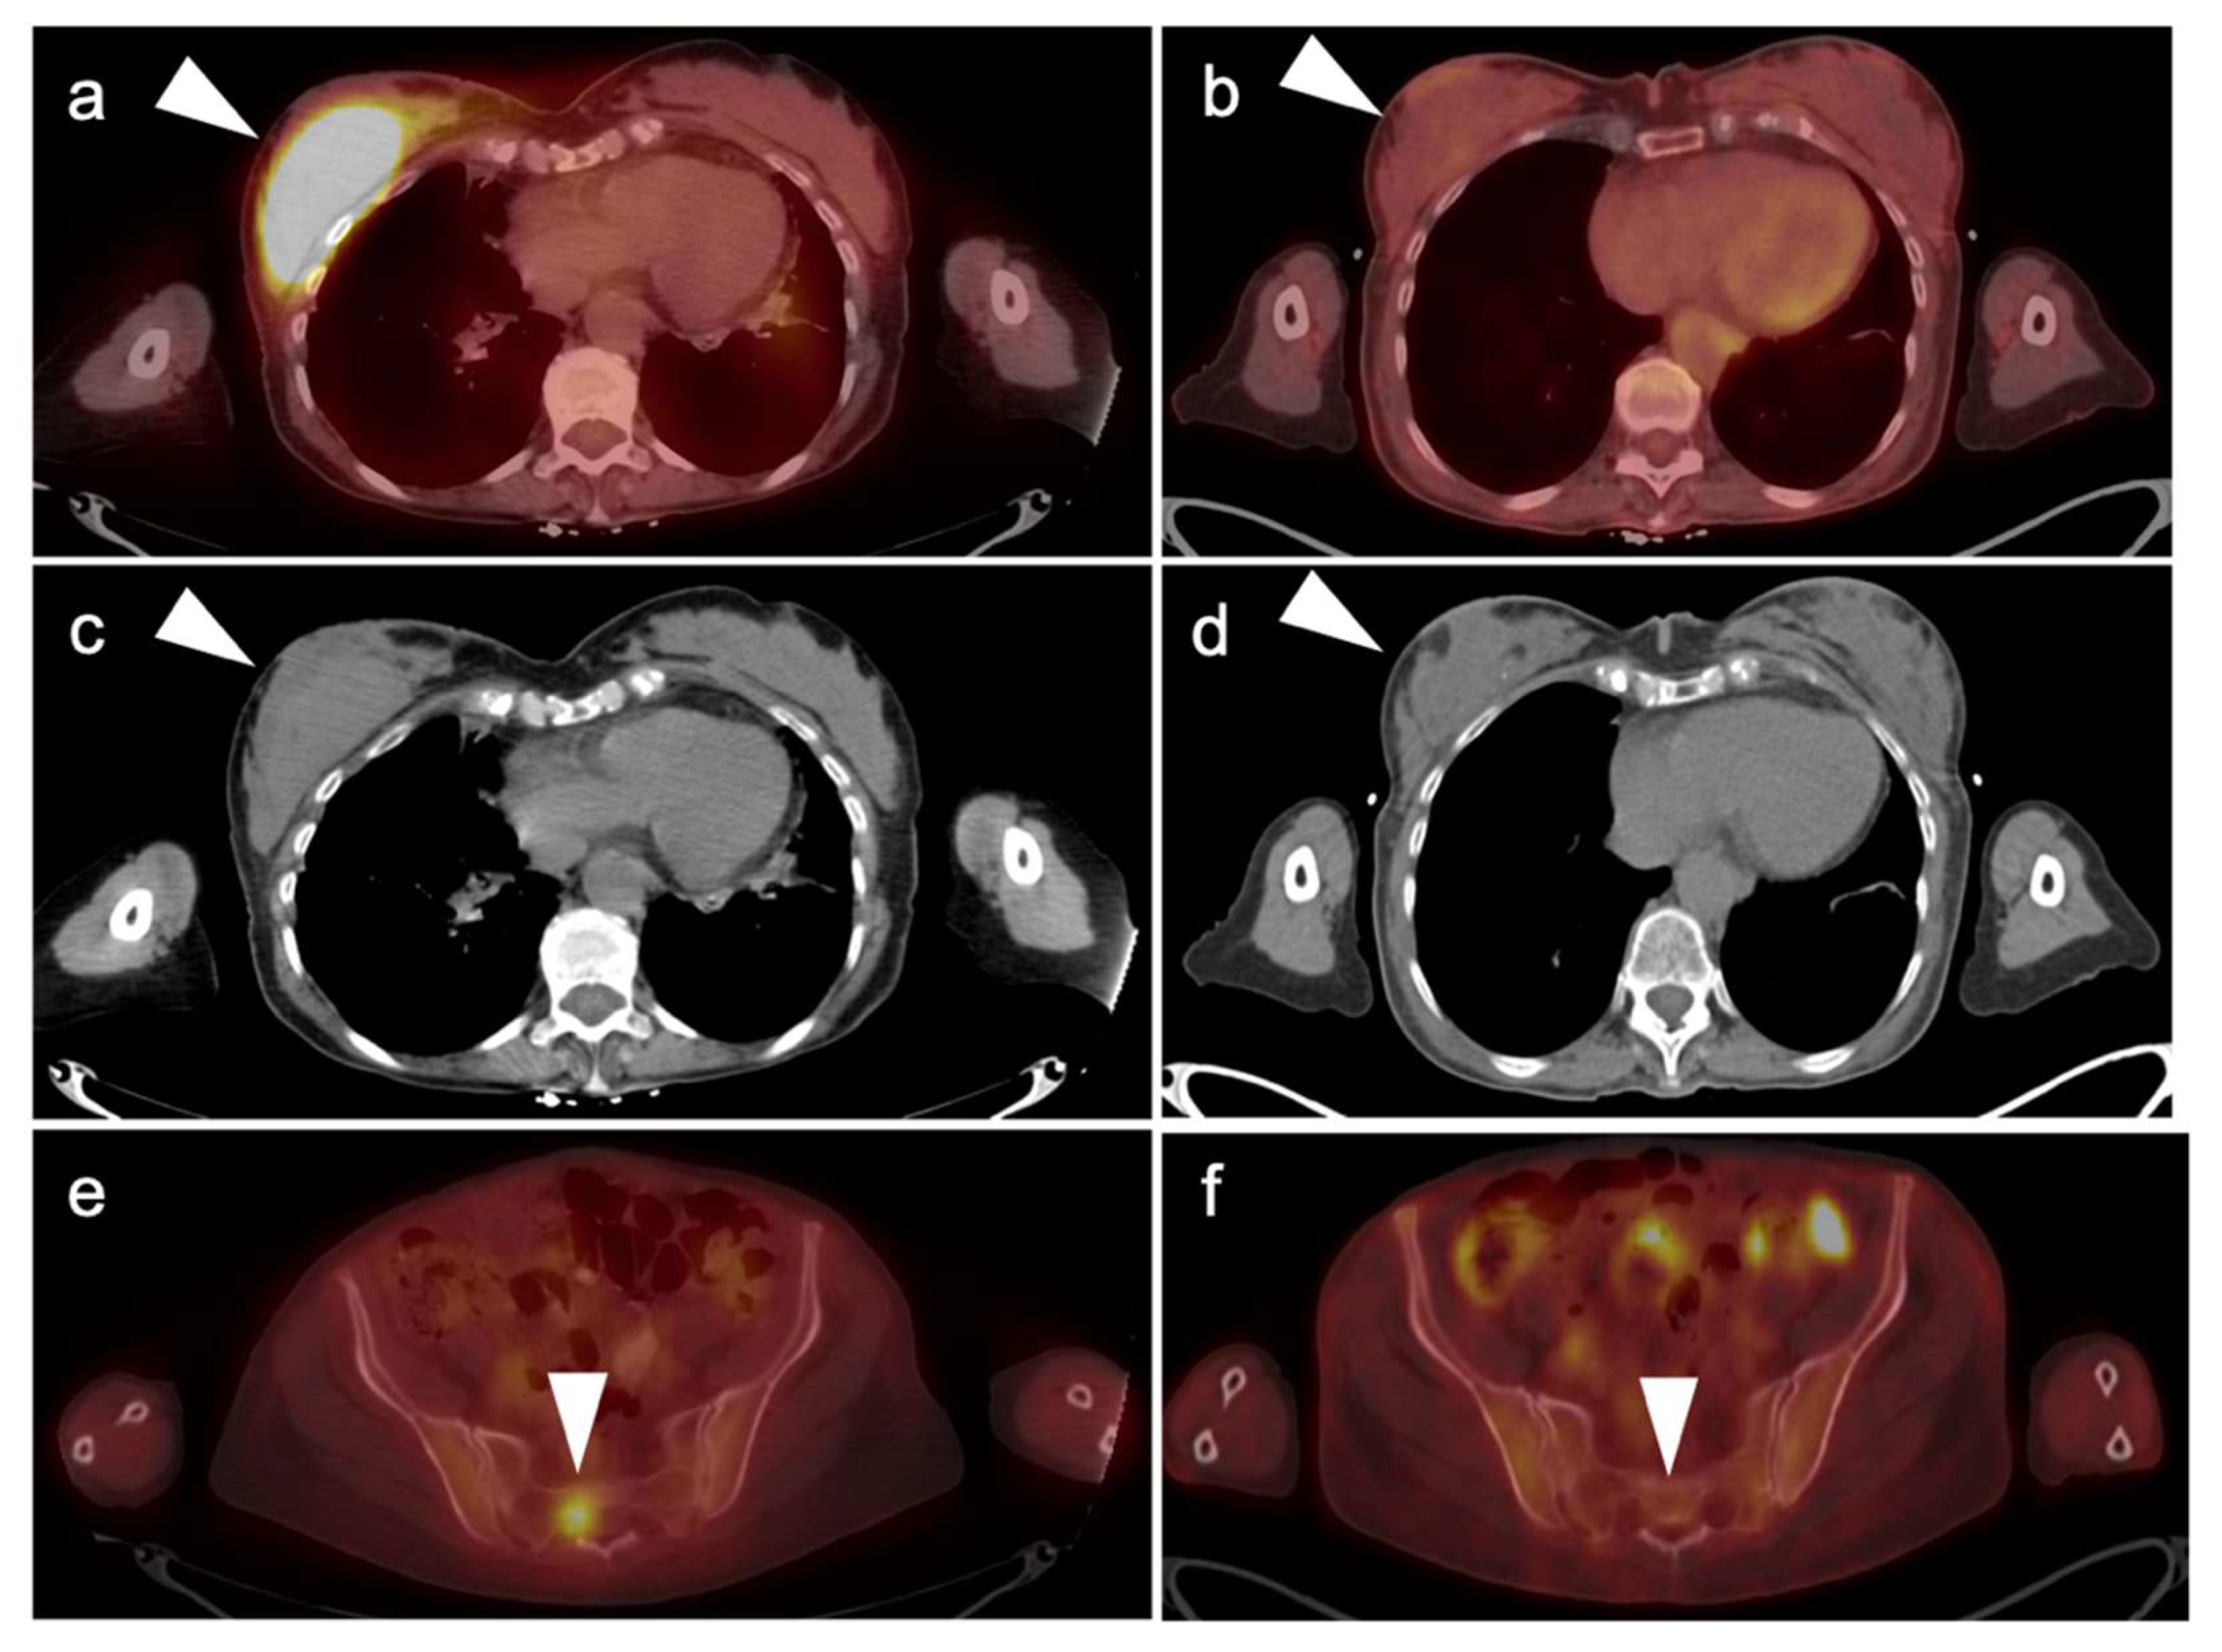

5.5. Invasive Ductal Carcinoma

The most common subtype of breast cancer is invasive ductal carcinoma (IDC) which accounts for most invasive breast cancer diagnoses [93,108] Invasive ductal carcinoma characteristically shows abnormal uptake on FDG PET-CT imaging and demonstrates higher uptake levels with larger tumors, higher grade tumors, metaplastic tumors, hormone receptor negative tumors, and triple-negative tumors (Figure 20) [109,110,111]. On FES PET-CT imaging, invasive ductal carcinoma would typically show uptake if the IDC is ER+. FES PET-CT may also depict heterogeneous ER expression in cases of metastatic IDC, wherein some but not all tumors have functional ERs. Invasive ductal carcinoma may be identified at a higher rate on FDG PET-CT imaging compared to invasive lobular carcinoma, discussed further below [110].

5.6. Invasive Lobular Carcinoma

Invasive lobular carcinoma (ILC) is a distinct molecular and pathologic entity from invasive ductal carcinoma and is the second most common type of breast cancer after invasive ductal carcinoma, comprising approximately 10–15% of invasive breast cancer cases in the United States [112,113,114,115,116]. Compared with IDC, ILC is more often difficult to identify on mammography, ultrasound, and FDG PET-CT [110,112,113,115,116]. ILC is also more often multifocal and bilateral compared with IDC [117]. Some ILC show hypermetabolic changes on FDG PET-CT as well as uptake on FES PET-CT (Figure 21). ILC may not take up FDG as readily as IDC for reasons that include lower tumor microvascularity, cellular density, proliferation rate, and number of glucose transporters [115,116,118,119,120,121,122,123]. ILC osseous metastases are more frequently present on FDG-PET-CT compared with IDC [118,119] as ILC osseous metastases are more frequently sclerotic, whereas FDG-PET-CT is more sensitive for lytic osseous metastases. Sclerotic ILC osseous metastases also may be indistinguishable from benign bone islands on CT at initial staging, thereby necessitating biopsy or imaging follow-up for confirmation of osseous metastatic disease [118,119]. Metastatic with of ILC may also occur at unusual sites, such as the stomach, uterus or colon [124].